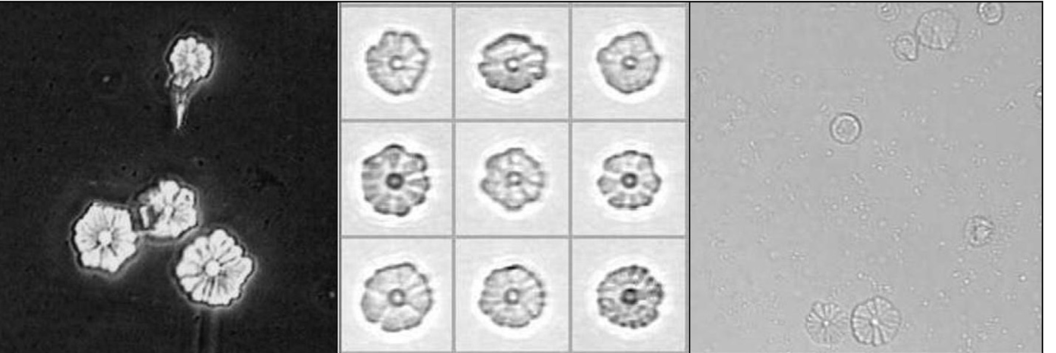

2003 年 3 月 25 日,罗马 Policlinico A.Gemelli 临床实验室发现了一种非常罕见的结晶尿(图 1A 和图 1B),结晶的形状让人想起雏菊(图 2 )。

事实上,它们是由 6 到 13 个不同宽度的三角形组成的,直径大约 15 到 38 μm、有明确的边分隔,其顶端向中央圆形结构汇聚,包含一个中心点,可以是透明的,也可以是深色的。G.B.Fogazzi 等 [1] 将这种具有「雏菊状」外观和非双折射的结晶定义为「雏菊状结晶」。

目前,雏菊状结晶已经在世界上多个国家的实验室被发现,我国尚未见报道。这种结晶主要见于女性、所有年龄段、碱性尿液、不同的尿比重中。此外,在狗的尿液中也发现了雏菊状结晶 [2],表明它们的出现并不只局限于人类。

2017 年,G.B.Fogazzi 等 [5] 报道了 「雏菊样」的结晶(图 3),红外光谱显示其结构含有碳酸盐离子,不同于碳酸钙(方解石),也不同于其他形式的钙碳酸盐(即文石和球霰石),X 射线显微分析可能有助于澄清这一问题,但不幸的是,作者同样也没有对其进一步进行分析鉴定,仍然需要进一步的病例来阐明「雏菊样」结晶发生的频率、临床意义,尤其是准确的成分。